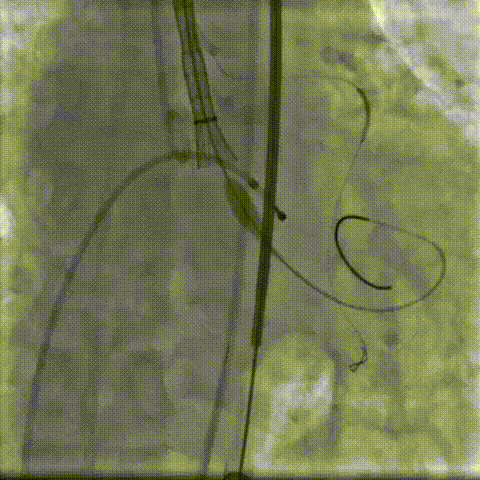

术中影像:

双侧侧髂血管造影血管纤细

LCA保护下18mm球囊预扩,扩张充分,瓣叶向LCA开口偏移;输送器过弓顺利。

瓣环下精准定位稳定释放,瓣膜工作位造影考虑瓣叶推挤LCA阻挡临界状态,释放“烟囱支架”。

瓣膜稳定脱钩,20mm球囊后扩,“烟囱支架”Kissing,后扩后支架形态改善。

左髂动脉“翻山“,造影+覆膜支架预备伴随保护下顺利退鞘,造影观察无血管损伤,手术顺利结束。